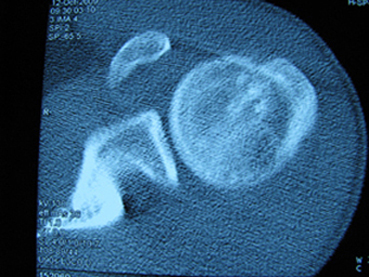

标题: X6404B:肱骨骨质破坏(CT片) [打印本页]

标题: X6404B:肱骨骨质破坏(CT片)

男,50岁,左肩部轻微疼痛,活动不便5个月就诊,近十天加重,无红肿热,间断理疗治疗无好转,既往5个月前左肩轻微拉伤史

骨巨?动脉瘤样骨囊肿?

内生软骨瘤。

内生软骨瘤。

内生软骨瘤?-----------

年纪大了,先要排除转移瘤。

髓腔内软组织肿块并斑片状钙化,考虑高分化软骨肉瘤可能性大。

考虑骨巨或动脉瘤样骨囊肿。

内生软骨瘤可能性大,期待结果。

孤立性骨囊肿。

内生软骨瘤可能性大

其内可见钙化,考虑软骨源性肿瘤,内生软骨瘤可能

但由于年龄较大,恶性软骨肉瘤待排

肱骨头内巨大软组织肿块并斑片状钙化,内生软骨瘤?骨巨细胞瘤?软骨粘液样纤维瘤?期待结果!

髓腔内软组织肿块并斑片状钙化,考虑高分化软骨肉瘤可能性大。

内生软骨瘤可能性大

肱骨头内巨大软组织肿块并斑片状钙化,内生软骨瘤?骨巨细胞瘤?软骨粘液样纤维瘤?期待结果

考虑内生软骨瘤?骨巨细胞瘤?

内生软骨瘤?骨巨细胞瘤?

先要排除转移瘤。